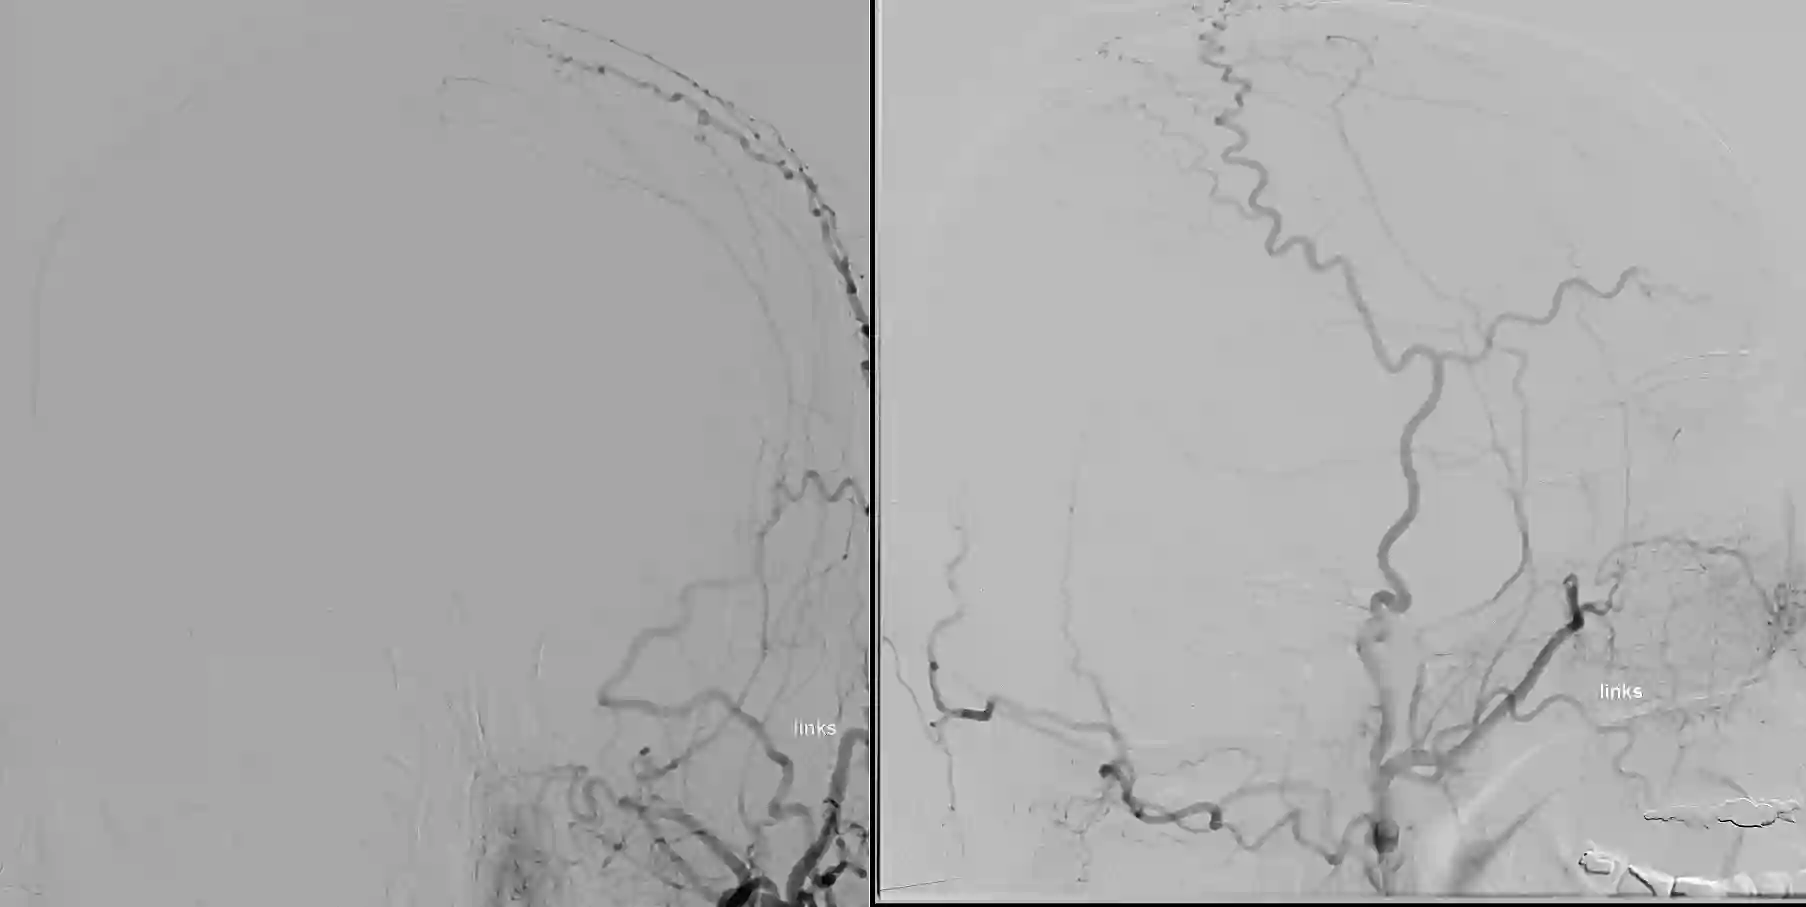

Bildgebung

Die Arteria carotis externa lässt sich in verschiedenen Bildgebungsmodalitäten wie MRT- als auch CT-Bildgebung darstellen. Die optimale Darstellung kann mit einer digitalen Subtraktionsangiographie erreicht werden.

Angiographie arteria carotis externa

Selektive Angiographie der Arteria carotis externa mit Darstellung der kraniellen Arterienäste.